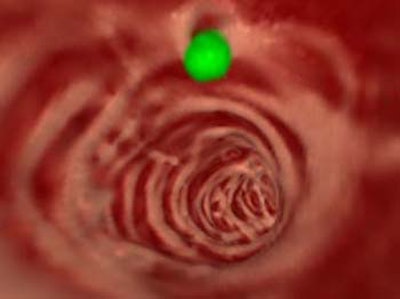

| Above, 3-D endoscopic view of the same CAD result. |

In the volume-rendered endoscopic views, voxels with the shape-index values corresponding to the cap, saddle/ridge, and other classes are colored green, pink, and brown respectively, enabling clear delineation of CAD-detected polyps from other structures.